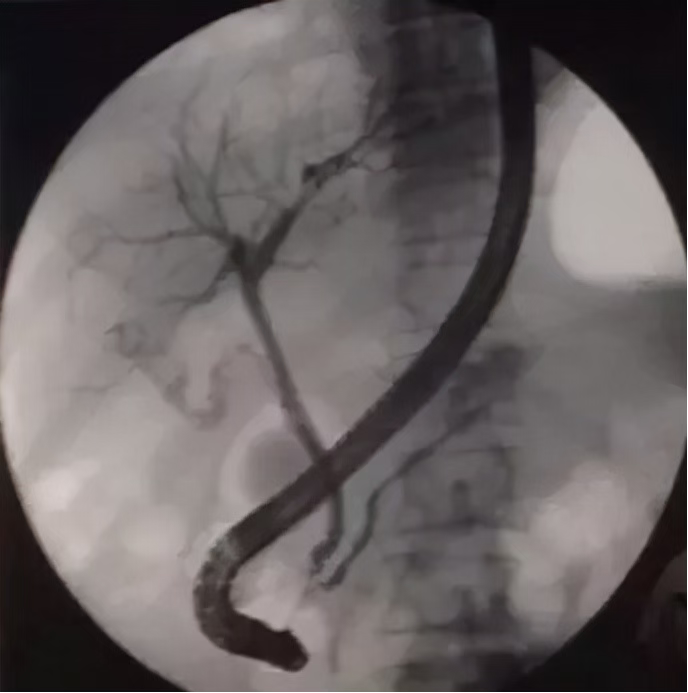

巨大胆管结石克星之---Spyglass

ERCP是内镜微创治疗技术的典范代表。近年spyglass的出现是一个亮点,其可在直视下进行胆胰管内活检甚至碎石治疗,突破了原内镜治疗的盲区,ERCP又焕发了新的可能。今年,我院率先引进了河西地区第一台(胆道镜)spyglass 为当地区胆管结石患者带来了福音。患者宋某于入院数3年前因腹痛就诊当地医院完善相关检查诊断胆管结石伴有胆管炎,因患者胆管多发并且结石大于1.0cm,ERCP球囊及网篮取石困难而无法取出,后多次就诊我科行ERCP及胆管支架置入。2023年3月该患者再次并发胆管炎而就诊我科。十二指肠乳头处可见支架一枚,切开型乳头,拔除支架。插管成功后,造影示胆总管扩张,其内见数个充盈缺损影,最大约1.2x1.0cm大小。Spy-Glsss见胆总管褐色结石,碎石后,引入直径1.4cm扩张球囊扩张乳头口,扩张成功后以取石球囊分次取出数块褐色结石数枚,另分次取出大量泥沙样结石,过程顺利。